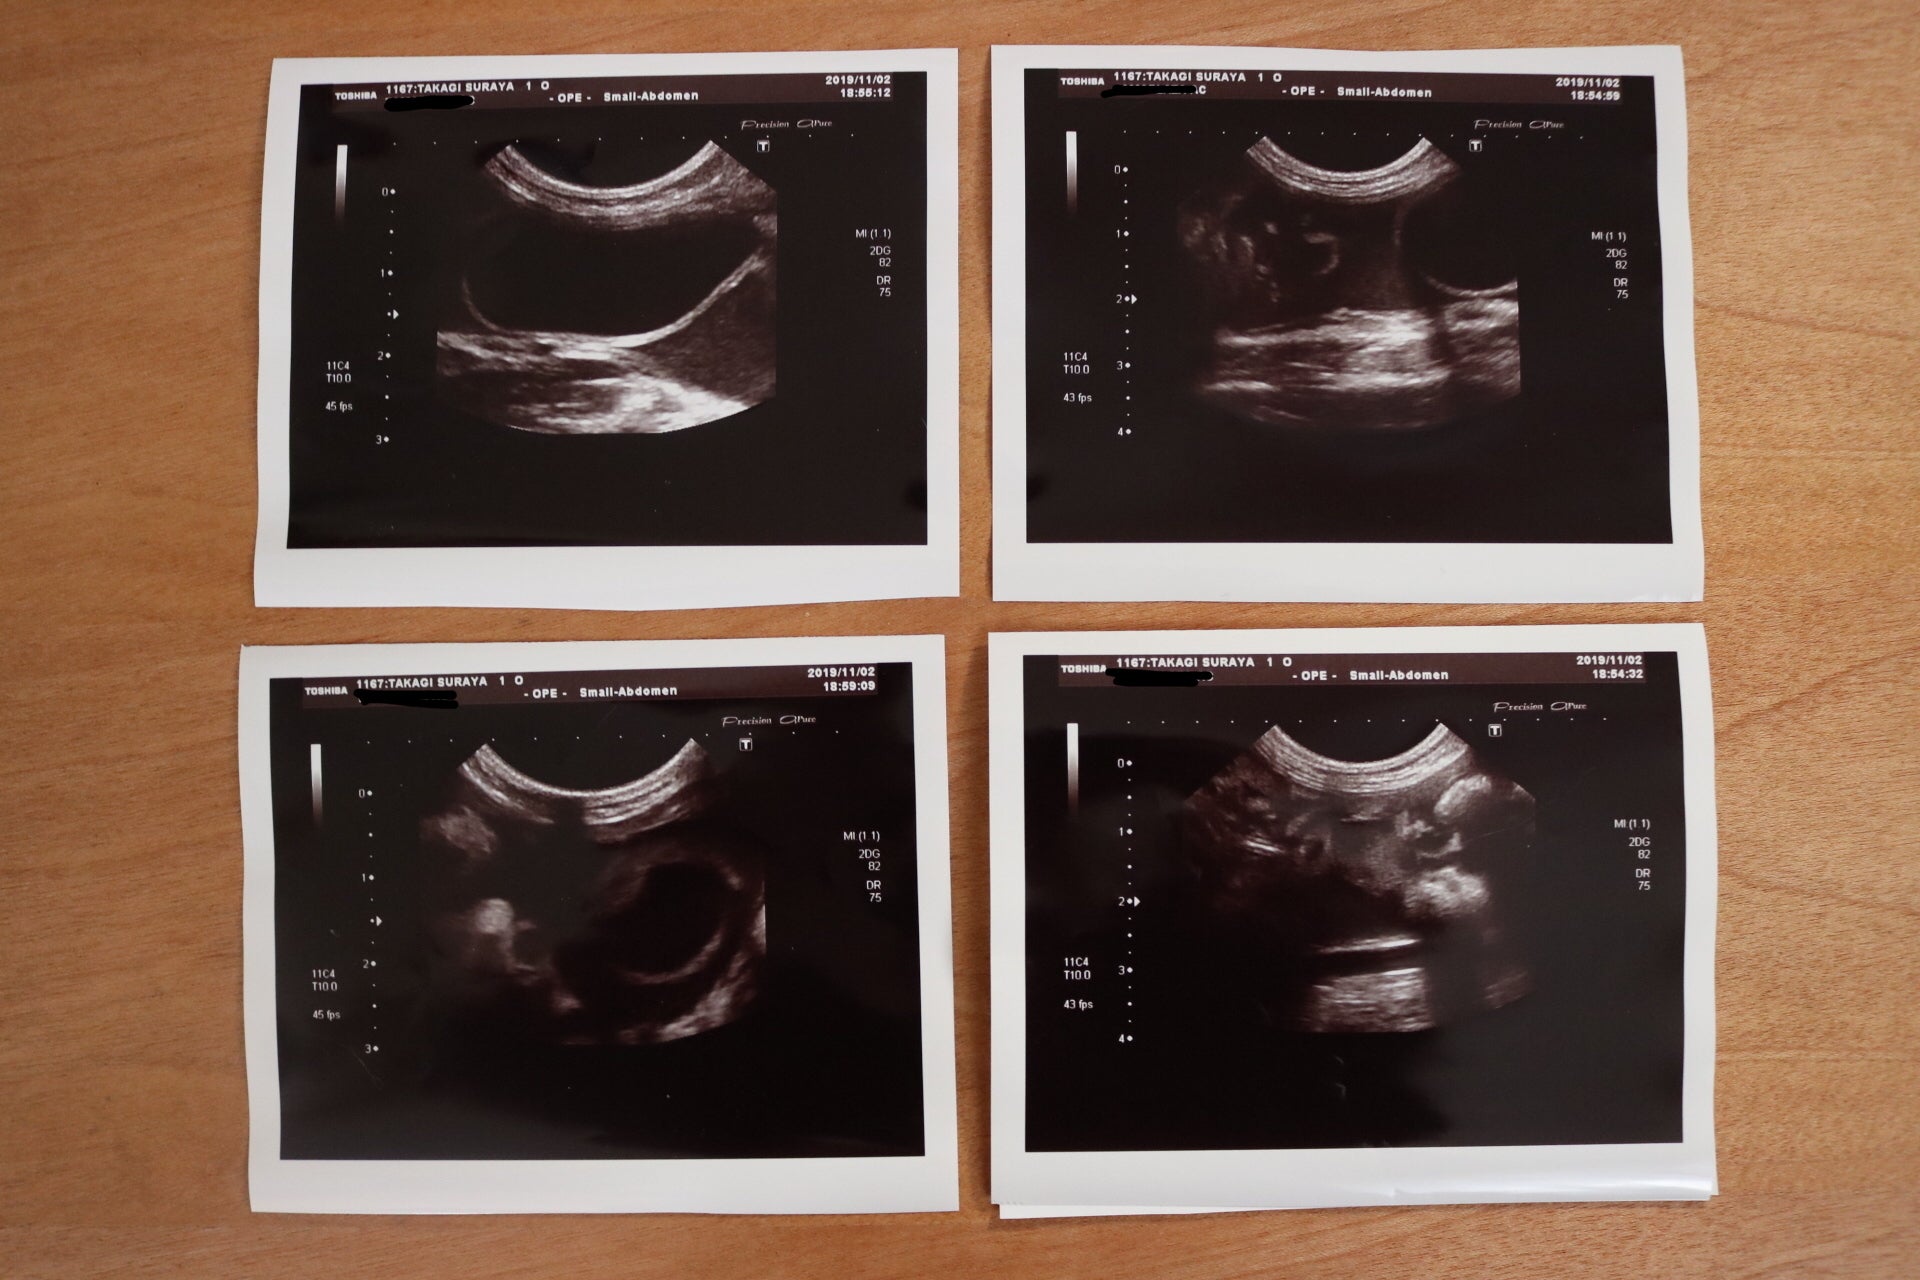

今回、スラヤさんを病院に連れて行くきっかけになったのは、血尿を発見したためです。膀胱を調べるためのエコーで、下腹部に僅かに溜まる腹水を発見することができました。

このFIPですが、ウェットタイプとドライタイプの2種類に大別され、スラヤさんはこのウェットタイプにあたります。血管からタンパク質が漏れ、体液として溜まってくるのがウェットタイプの特徴です。